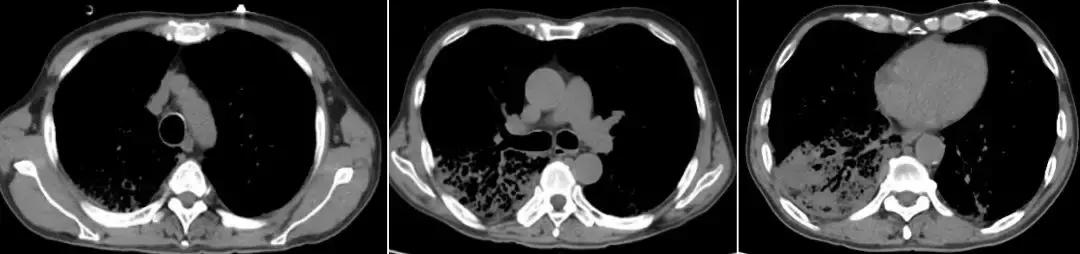

男,67岁,急性病程;发病前有旅游病史;主诉:发热、干咳伴呼吸困难2天,加重1天;查体:体温38.3℃,心率96次/分, 呼吸35次/分,血压98/63mmHg,SpO2 88%(FiO20.37),急性病容,呼吸急促,左肺呼吸音粗,右下肺呼吸音减弱,双下肺可闻及湿啰音;肺部CT示双下肺渗出、实变影,动脉血气分析提示I型呼吸衰竭。

2017-9-26

2017-9-29

支气管镜检查示

双侧气管黏膜充血,可见大量脓黄痰,左下肺基底段灌注生理盐水50ml,回收20ml,送检细菌和真菌涂片、培养;7项呼吸道病原体;EB病毒核酸、巨细胞病毒核酸;抗酸杆菌涂片及染色、结核分枝杆菌鉴定及药敏。最终结果回报:H1N1和金黄色葡萄球菌(MSSA)。降级抗生素为阿莫西林克拉维酸钾联合奥司他韦抗病毒治疗,患者症状好转出院。

经验教训

甲型流感病毒感染后可能出现继发细菌(肺炎链球菌、金黄色葡萄球菌、流感嗜血杆菌等)和曲霉感染,一定注意病原检测,不要过度依赖于强大的抗细菌药物。